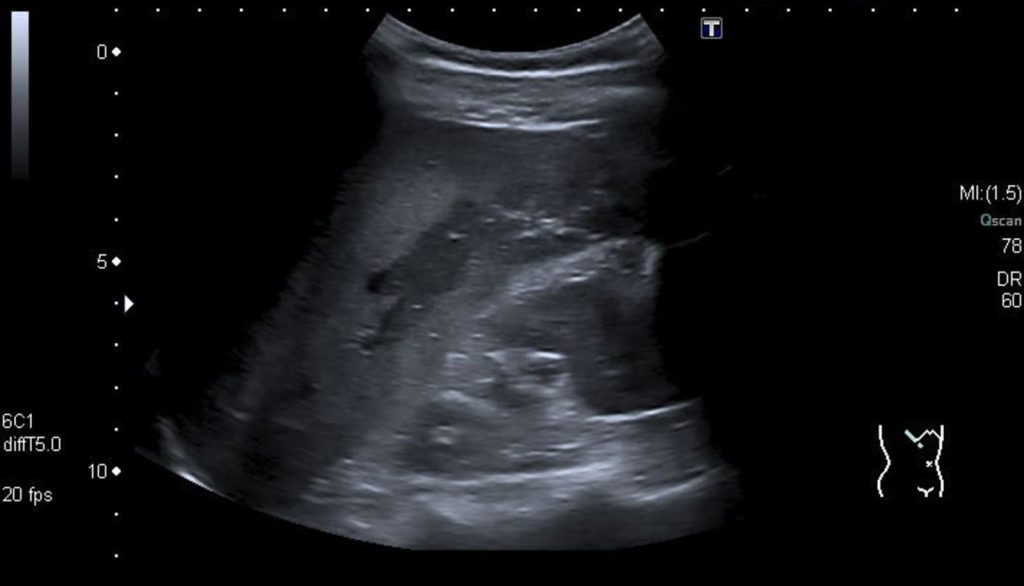

آبسه کبدی پیوژنیک

آبسه کبدی پیوژنیک یک بیماری نادر است که با تجمعهای منفرد/ چندگانه مملوء از چرک در کبد مشخص میشود. این عفونت توسط باکتری ها ایجاد میشود و معمولاً چند میکروبی است و اکلای و کلبسیلا پنومونی ارگانیسمهای اصلی ایجادکننده هستند. در بیشتر موارد صعود عامل عفونی در اثر وجود مجاری صفراوی غیرطبیعی اتفاق میافتد (کلانژیت ناشی از سنگ مجرای صفراوی مشترک، تنگی مجاری).